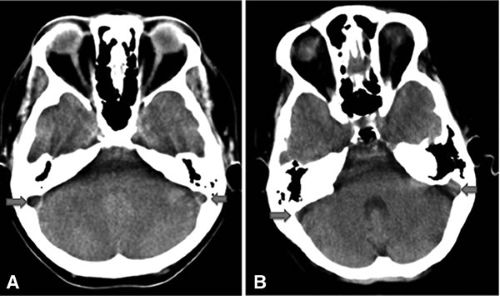

- Care must be taken to differentiate thrombosis from congenital sinus hypoplasia or atresia, which can appear similar (lack of flow) on venography. Evaluating the bony grooves for the sinuses on CT can help distinguish these (Figure A vs. B in the image below).